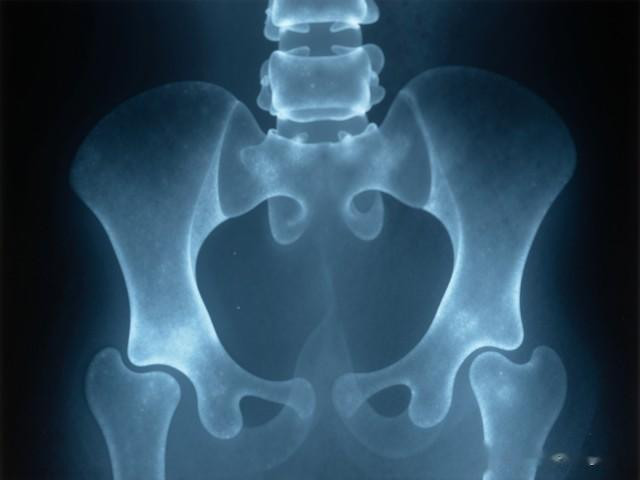

旧年《中华老年医学杂志》一项阴私3万多名老东说念主的沟通明确指出:这类药物与髋部骨折、通晓功能着落权臣关连。你可能没意志到,深宵起夜一个蹒跚,就可能把冷静晚年摔没了。